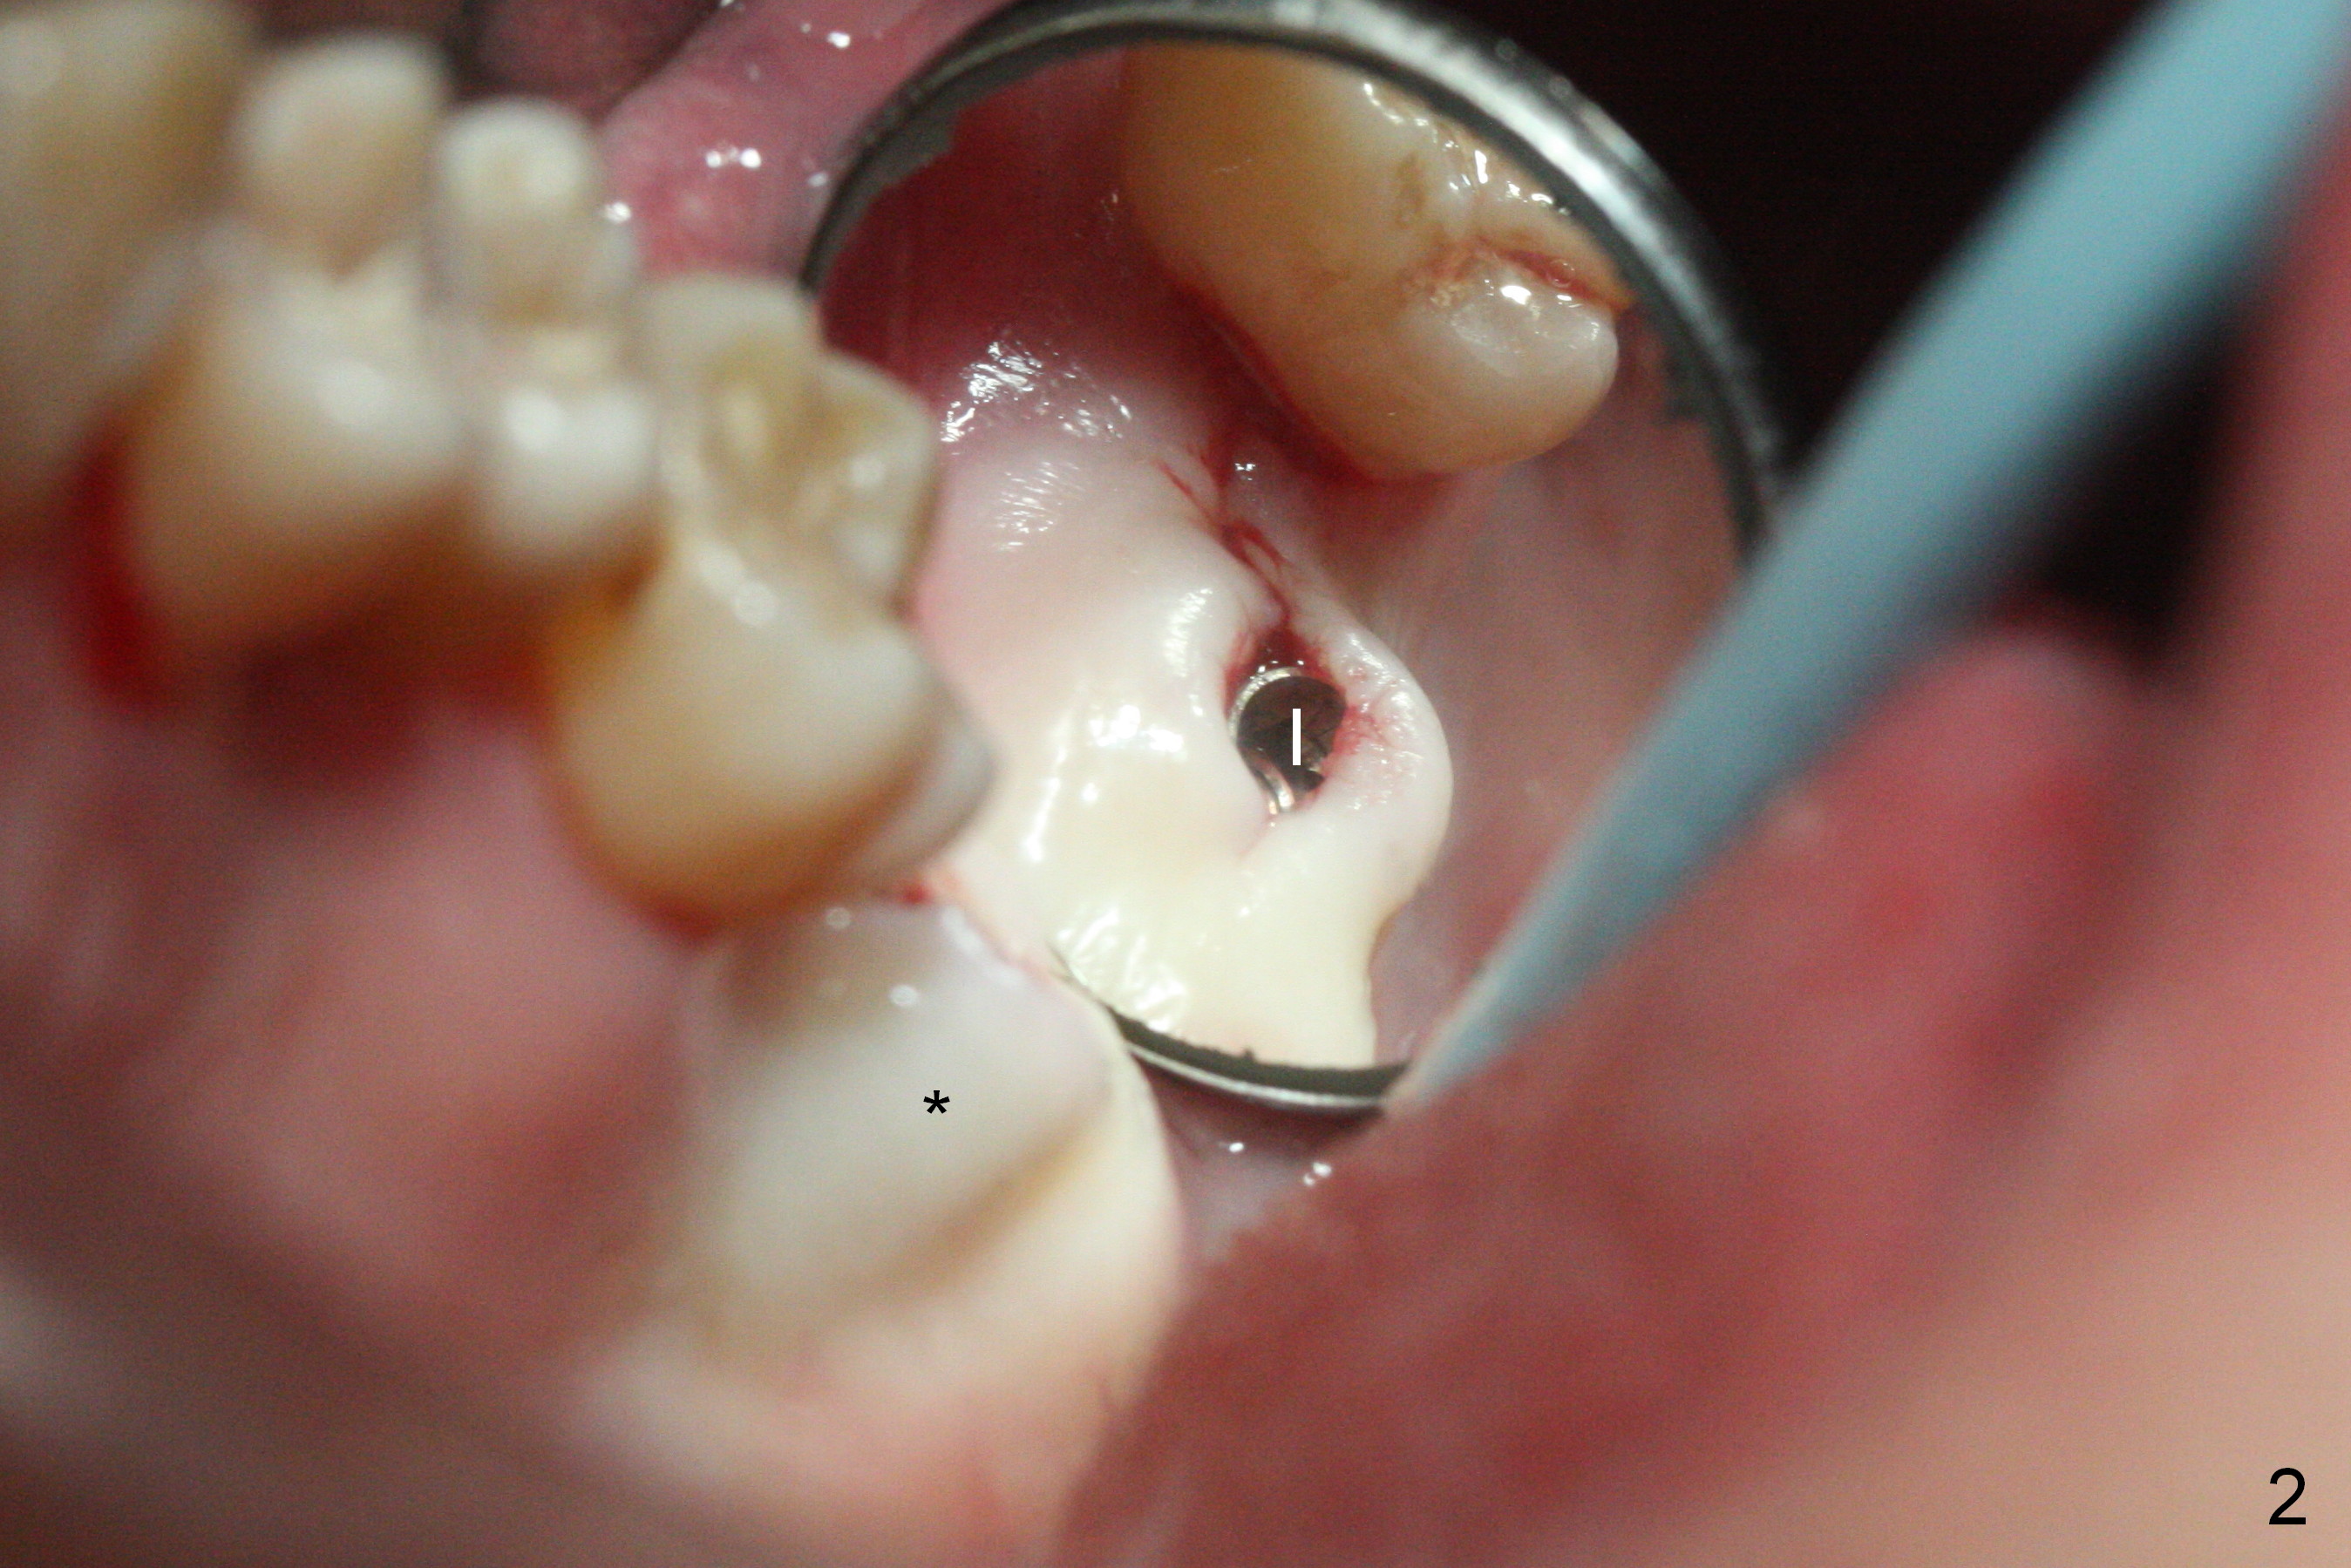

Initial osteotomy at the site of #15 for 4x11 mm dummy implant is created by #15 blade, Magic Split and Magic Expanders (ME) 3.0 and 3.8 mm (flapless, Fig.1,2, 4A (blue circle)). The implant is palatally displaced. Release incision confirms the deviation. A new osteotomy is established with 1.6 mm pilot drill in the middle of the site (Fig.4A (occlusal view) red circle). Distal to the new osteotomy is the incompletely healed socket (brown circle). As the osteotomy is enlarged by ME until 4.3 mm and placement of 4.5 and 5.0 mm dummy implant and of 5.5x9 mm definitive one (Fig.3, 4B large red circle), the osteotomy gradually deviates distopalatally. Introspectively, the new osteotomy should have been placed more buccomesially (Fig.4C red circle) so that the final osteotomy may end up normally (Fig.4D large red circle).

Prior to implant placement, two pieces of PRF plug are inserted. The insertion torque is <15 Ncm. A cover screw is placed. The distopalatal defect is covered by allograft and 1 piece of PRF membrane. There is no intraop sinus membrane perforation or nasal hemorrhage postop.

Because of unfavorable implant/crown ratio (Fig.3), the implant will be uncovered 6-7 months postop. An angled abutment is expected to correct the distopalatal displacement of the implant. In the meantime orthodontic treatment should start to align the malpositioned anterior teeth before extraction and implantation.